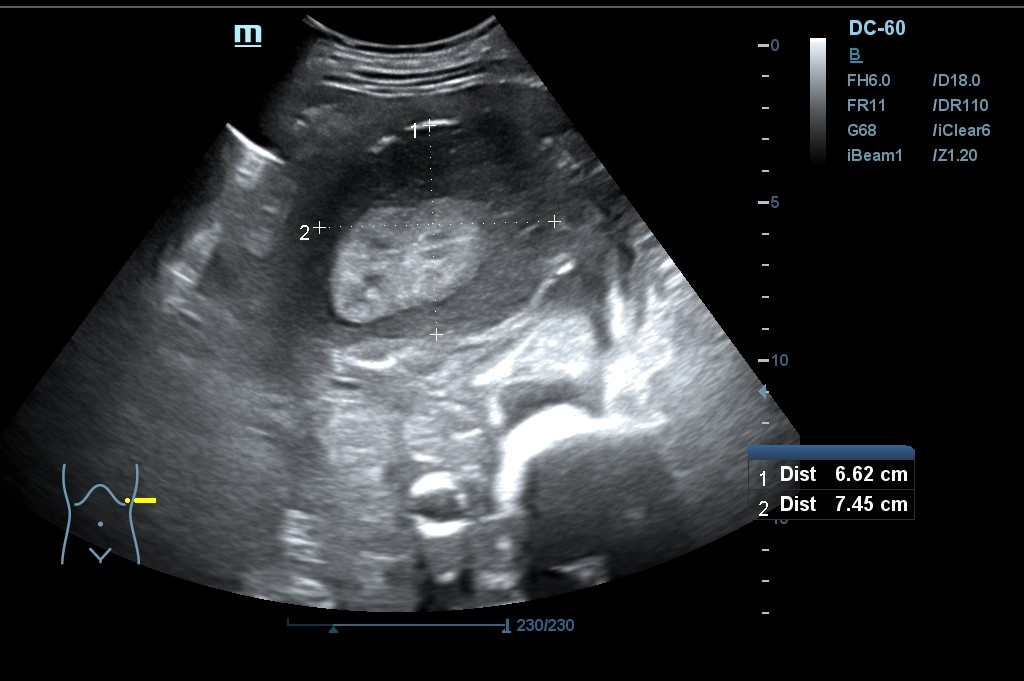

Hallazgo de lo que impresiona de nefromegalia izquierda de aproximadamente 14 cm con hidronefrosis bilateral grado 2.

Se realiza una nueva ecografía en la que se confirma la ascitis y persisten las alteraciones renales.

Tras la segunda ecografía se deriva a la paciente a la Unidad de Diagnóstico Rápido de Medicina Interna donde ingresa para completar estudio. Tras ecografía en la que informan de extenso tejido hipoecoico periaórtico y perirrenal izq. (nefromegalia izq.) con extensión nodular al mesenterio, se establece la sospecha de síndrome linfoproliferativo, así como en un TC posterior y que se confirma como Linfoma No Hodgkin mediante biopsia.